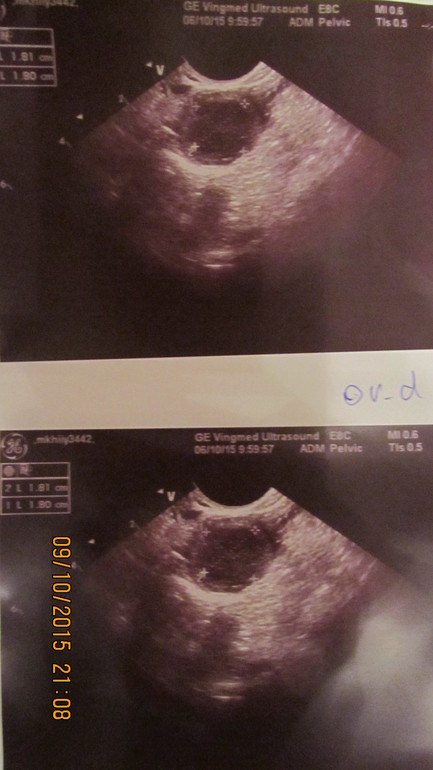

ФолликулометрияДевочки, в этом месяце я делала фолликулометрию. в ПЯ рос ДФ. 5дц - 9 мм, Э - 3,5 мм. 12 дц - 14 мм, Э - 5 мм. 14 дц - 17,7 х 12,5, Э - 7 мм жидкость не опр-ся (фото прилагаю) 19 дц - Э - 10, 7мм, сначала она сказала желтое тело, потом исправила на "Жидкостное образование 17 х 19 мм с геторогенным содержимым. Свободная жидкость в ПМП определяется прослойка - 10 мл (мм?)

сначала она сказала желтое тело, потом исправила на "Жидкостное образование 17 х 19 мм с геторогенным содержимым. Свободная жидкость в ПМП определяется прослойка - 10 мл (мм?)